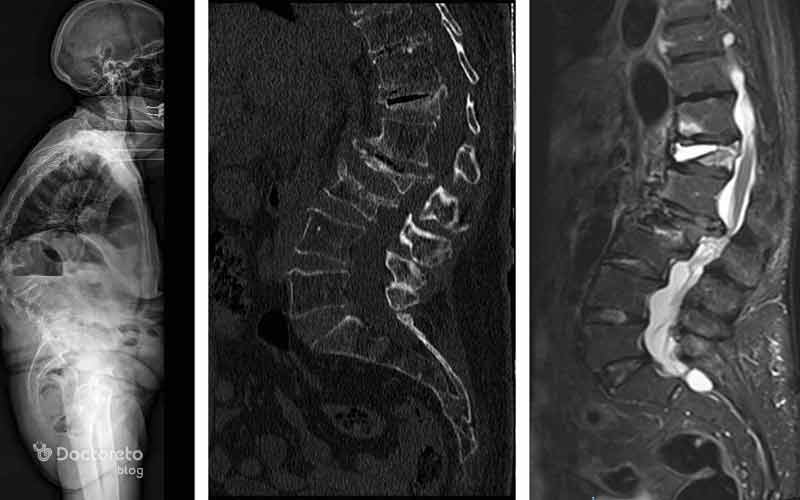

روشهای دیگری هم میتوانند به تشخیص اولیه بیماری پوکی استخوان کمک کنند که یکی از آنها سی تی اسکن و تصویربرداری ام ار ای است. سی تی اسکن کیفی یا QCT دوز اشعه بالاتری دارد و فقط در موارد خاص استفاده میشود. این روشها خصوصا برای تشخیص شکستگیهای استخوانی در ستون فقرات کاربرد دارند.

در عکس پوکی استخوان به دست آمده از MRI، سیگنال مغز استخوان ظاهری ناهمگن با جایگزینی پراکنده و یکنواخت مغز استخوان با چربی (سیگنال T1 بالا) دارد.

یکی از مشکلات ستون فقرات، پوکی استخوان در این ناحیه است. در عکس پوکی استخوان ستون فقرات میتوان شکستگیهای احتمالی در استخوانها را تشخیص داد. جا به جایی مهرهها، شکستگیهای فشاری و مهرهای و نازک شدن ترابکولاهای افقی در جسم مهرهها، از جمله مواردی است که میتوان در تصاویر به دست آمده از ستون فقرات، از آنها برای تشخیص پوکی استخوان استفاده کرد.